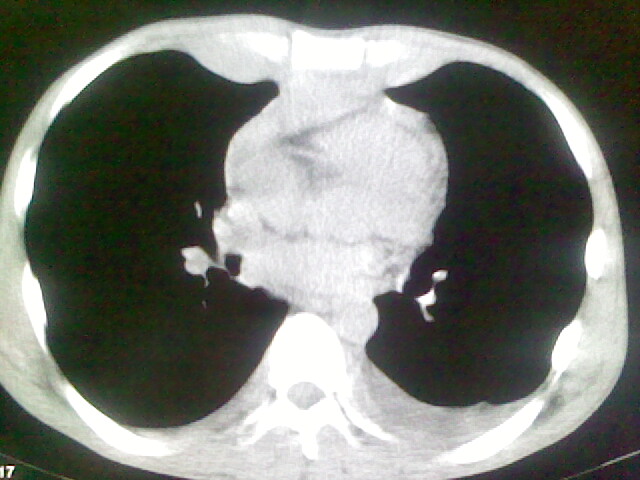

以下是引用杀毒软件在2008-9-3 6:11:00的发言:[br]侵袭性胸腺瘤------一般不侵到气管旁[br][br]考虑----纵隔淋巴瘤,心包及胸膜受累

以下是引用随光逐影在2008-9-3 7:07:00的发言:[br]1)考虑淋巴瘤可能。2)双侧胸腔积液(以左侧为甚)。3)心包积液。